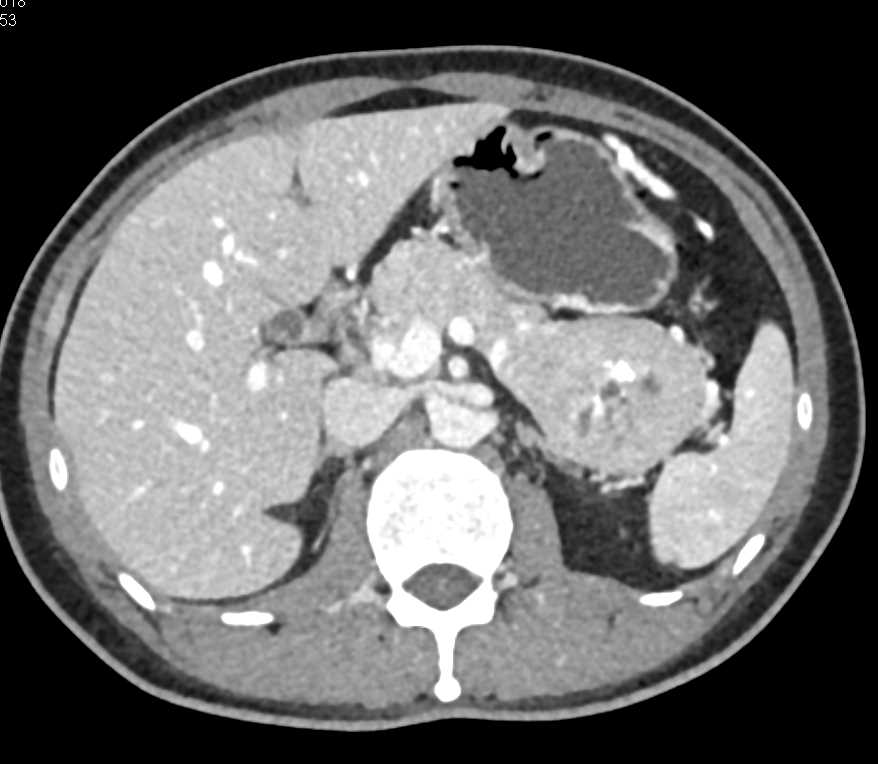

PNET Tail of the Pancreas